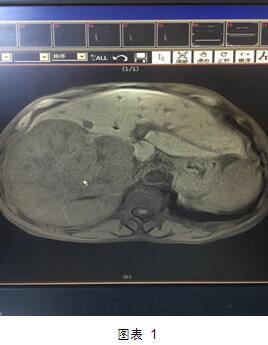

但是近日,我院肝膽外科就做了一次這樣的大挑戰(zhàn)?;颊呤且晃?0多歲的老者,老人家入院后診斷為肝右葉巨塊型肝癌(圖1)。這個癌塊已經占據整個肝臟的60%,而且腫瘤侵及第一肝門、第二肝門,門靜脈有癌栓形成。這種情況在臨床上已經屬于中晚期肝癌,手術根治困難,風險極大。然而不手術切除的話,老人家的生存期恐怕不會超過三個月,而且會一直處于癌癥的折磨之中。